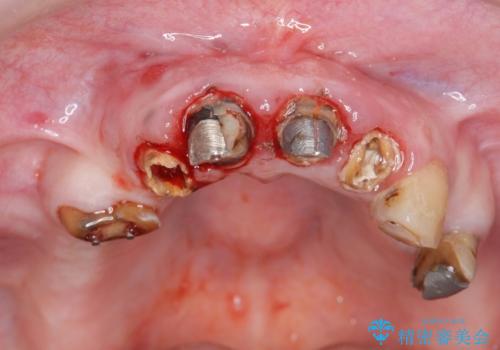

多発した虫歯による咬合崩壊 インプラントを用いた全顎治療

歯の破折・再発した大きな虫歯・根尖病変・歯の欠損、これらの問題を根管治療・歯周外科・インプラント治療・セラミック補綴を行うことで一つづつ解決し安定した咬合状となるよう治療を進めます。

インプラント治療の注意事項(リスク・副作用など)

- 外科手術のため、術後に痛みや腫れ、違和感を伴います

- メンテナンスを怠ったり喫煙により、お口の中に大きな悪影響を及ぼすインプラント周囲炎等にかかる可能性があります